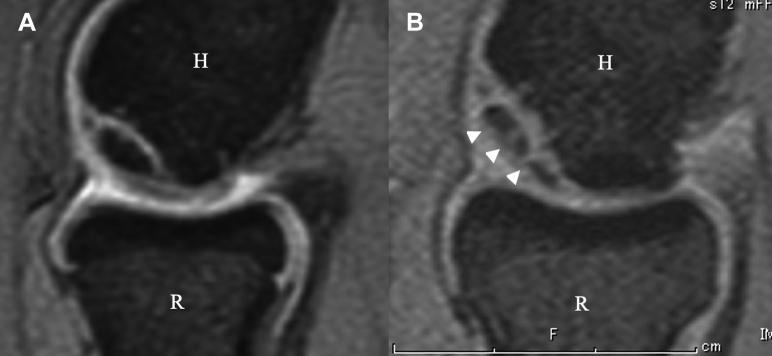

There were 26 and 6 patients in Groups A and B, respectively. Two patients did not obtain complete union. Clinical outcomes improved after the procedure. In univariate analysis, delayed union was associated with larger major diameter ( = .0004) and more depth ( = .03) of the osteochondral fragment measured by computed tomography, the presence of osteosclerosis in the subchondral bed on X-ray imaging ( = .003), and the presence of comminution of subchondral bone on ultrasound imaging ( = .01). In multivariate analysis, there was a significant difference only in the major diameter of the osteochondral fragment ( = .03). Receiver operating characteristic curves analysis shows that if the major diameter of the osteochondral fragment is 11 mm or less, 85% of patients achieve complete union of the osteochondral fragments within 6 months.

A组和B组分别有26例和6例患者。2例患者未实现完全愈合。术后临床结果有所改善。单因素分析显示,延迟愈合与计算机断层扫描测量的骨软骨碎片较大的长径(P = 0.0004)和更深的深度(P = 0.03)、X线成像显示的软骨下骨硬化(P = 0.003)以及超声成像显示的软骨下骨粉碎(P = 0.01)有关。多因素分析显示,仅骨软骨碎片的长径存在显著差异(P = 0.03)。受试者工作特征曲线分析表明,如果骨软骨碎片的长径为11 mm或更小,85%的患者可在6个月内实现骨软骨碎片的完全愈合。